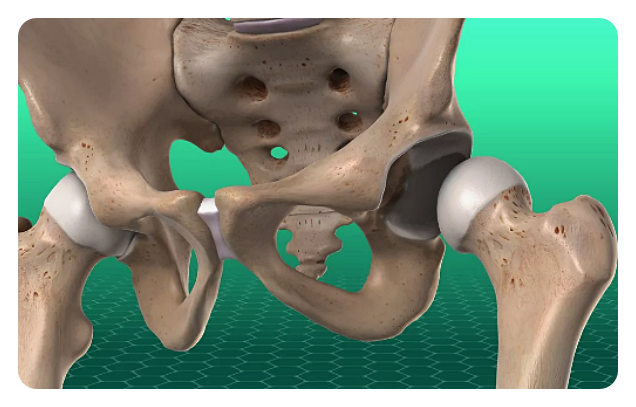

고관절은 몸을 지탱하고 움직이는 데 중요한 역할을 하는데, 골반과 대퇴골을 연결하는 관절입니다. 우리의 일상적인 활동에서도 이 관절은 걷기나 뛰기와 같은 움직임뿐만 아니라 체중을 지탱하고 다리를 움직이는 데에 필수적입니다. 그러나 나이가 들거나 부상 등으로 고관절이 손상되면 통증과 움직임 제한과 같은 문제가 발생할 수 있습니다.

인공관절 치환술: 이 수술은 고관절이 심각하게 손상되거나 통증으로 인해 일상 생활에 지장을 주는 경우에 시행됩니다. 이 수술은 손상된 관절을 제거하고 인공 관절로 대체함으로써 이루어집니다.